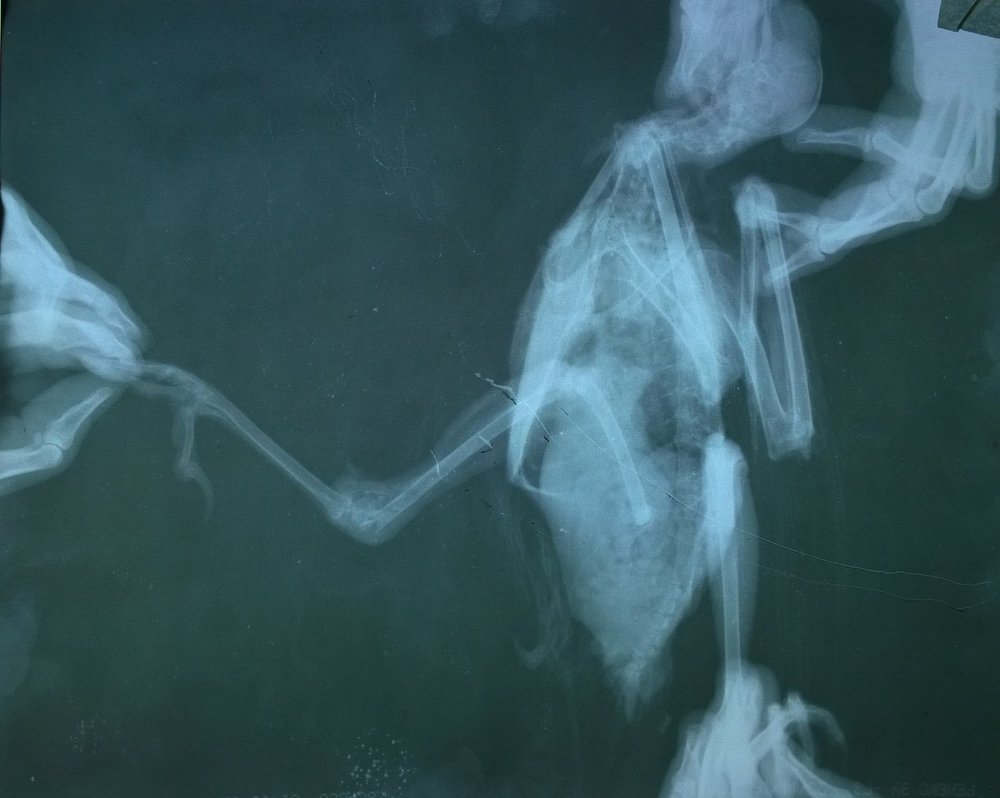

Доброго времени суток! позавчера вечером подобрала грача.Изначально. проблема с лапой. Только сегодня удалось сделать рентген. Отправили в другую клинику. Записаны на субботу на консультацию к хирургу по снимкам.Подскажите, пожалуйста, насколько все печально, исходя их снимков, что нужно делать и не нужно. и на сколько целесообразен в данном случае остеосинтез. Заранее спасибо